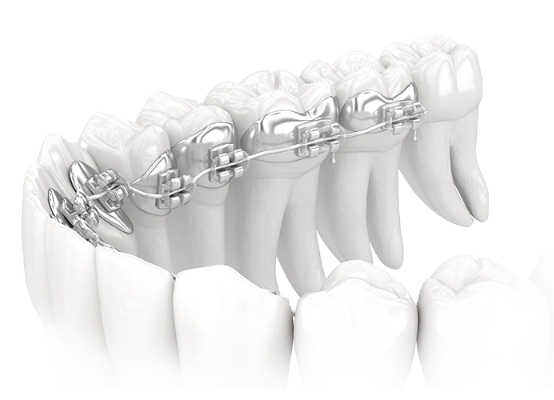

치료

환자가 치료 계획에 동의하게 되면 수차례에 걸쳐 교정 장치가 부착되며